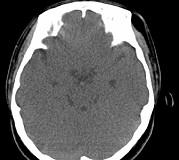

问题 女,31岁,在左眶外上缘发现一包块,质软,余所见无明显异常.如图所示病灶应诊断为()

选项 A.畸胎瘤 B.错构瘤 C.脂肪瘤 D.表皮样囊肿 E.淋巴管瘤

答案 C